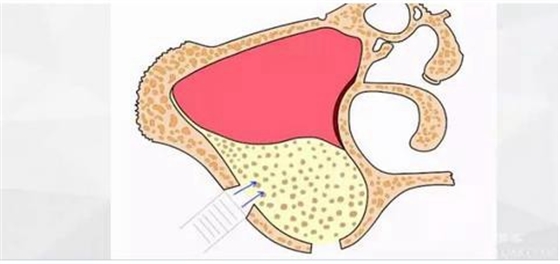

擴大窗口,此時因為上頜竇膜已經(jīng)與骨壁分離,所以打磨時不會損傷到膜。

進一步剝離。